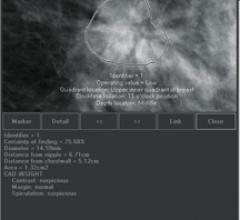

Despite decades of progress in breast imaging, one challenge continues to test even the most skilled radiologists ...

ECRI Institute released a report listing three key questions and the answers concerning breast-specific gamma imaging (BSGI; sometimes referred to as molecular breast imaging or MBI). The technology uses a specially designed gamma camera system to image the uptake of a tracer that emits gamma radiation (most commonly 99mtechnetium-sestamibi [MIBI]). MIBI is preferentially taken up by cancer tissue, and thus BSGI can be used to image breast cancer for a variety of clinical indications. Unlike X-ray mammography, BSGI is not affected by the density of breast tissue, and therefore it may be particularly useful for screening and diagnosis of breast cancer in women with dense breast tissue.

I can be more precise with the ATEC biopsy device,” explains Jason Gatewood, M.D., Lead Interpreting Radiologist at the Saint Luke’s South Hospital Goppert Breast Center. “I don’t have to force it, and that gives me more control of the needle allowing me to be precise.” Dr. Gatewood has experience with most of the biopsy devices available for ultrasound guidance, and prefers the ATEC vacuum-assisted breast biopsy device. “The ATEC biopsy device has multiple advantages which allow it to be used in any scenario for breast biopsy, including dense breasts, cystic masses, random masses and small lesions.”